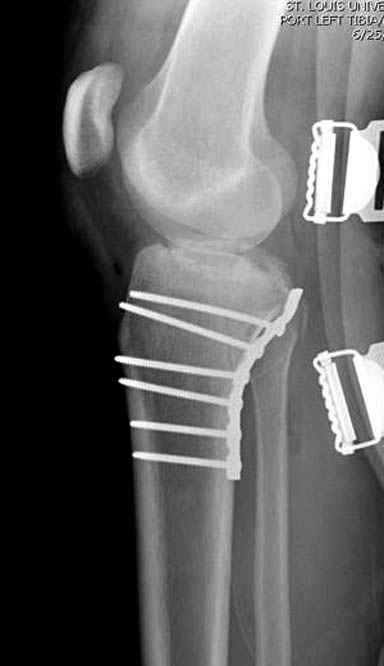

Уважаемые коллеги! В прошлую пятницу больной прооперирован - как и планировалось мыщелковая LCP от ChM. Малоинвазивно не получилось - один большой доступ :(. (но с минимальным скелетированием б/б кости). Наружный мыщелок собрали, но по контролю видно, что задне-медиальный отдел метаэпифиза смещен. Фиксировать не стали (?). 4-е сутки после операции - по м/тканям без проблем. Дополнительная иммобилизация синтетическим тутором.

Интересно услышать ваши мнения, анализ ошибок...

P. S. перелом диафиза на контроле не совсем захвачен, но проблем там нет. Приношу извинения за низкое качество Р-грамм - выполнены на сканере (фотоаппарат не работает :)) .

Трудно поверить, что разрекламированная Ортопедическая школа Восточной Украины позволяет такие странные снимки? На прямом снимке сохранен общий контур плато, но не известна судьба импрессии суставной поверхности. На полубоковой?, оставлен без репозиции задне-медиальный отдел, и навряд ли после такой фиксации можно удовлетвориться результатом.

Такая ситуация характерна для многих, когда принимается ошибочное решение, т.е пытаются фиксировать одним имплантом переломы двух мыщелков. Латеральная пластина приемлема только для тех случаев, когда сохраняется интактным медиальный диафизарный кортекс и отсутствует фрагментация на верхушке медиального перелома.